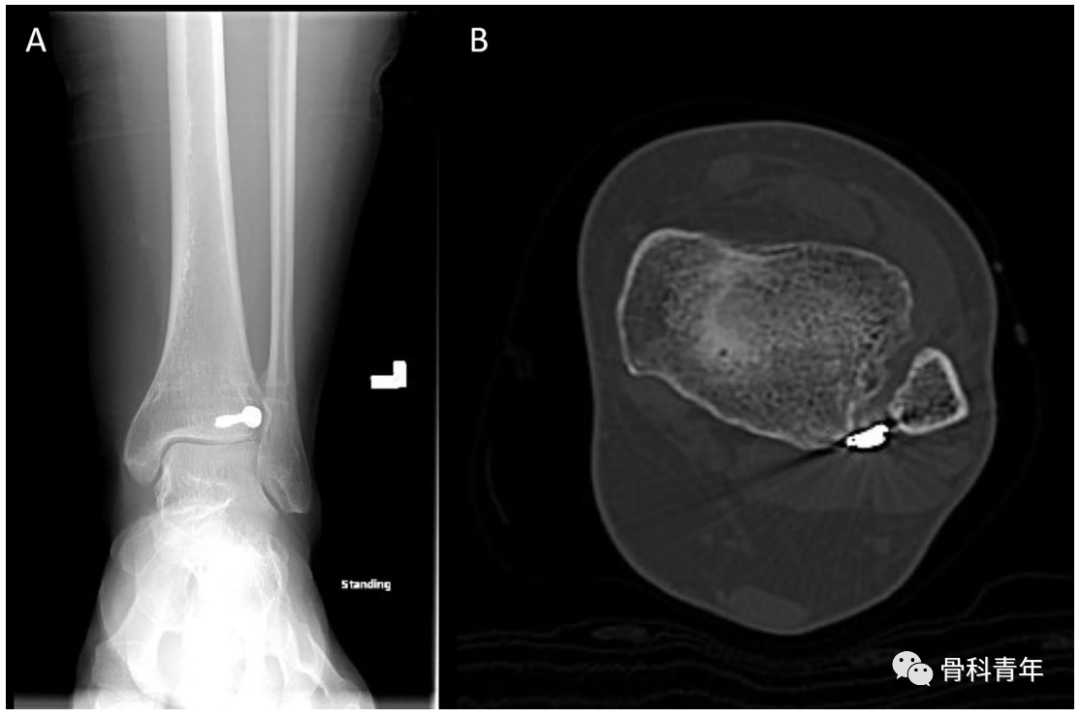

该例后踝螺钉穿入下胫腓的标本在CT横断中可明确。

依上述研究结果,在如下的后踝钢板固定中,透视钢板部分位于PVSL线外侧,有影响下胫腓风险,因此将钢板内移至PVSL线内。

▲ 图中白色虚线即为PVSL线。